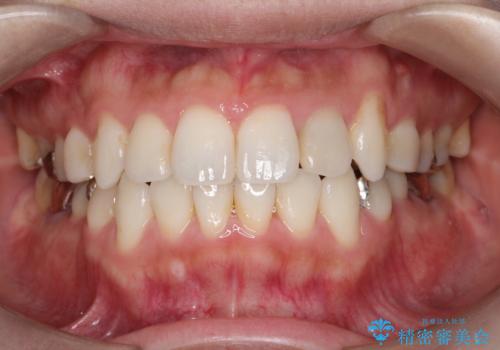

30代女性 前歯のがたつき